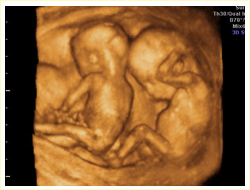

二:引進國際最高水平四維彩超,最低只需1820元。

省內唯一一臺美國GE-v730超高清四維彩超于2011年入駐省級重點婦產科中心——廬江康平產科醫院。現在每日預約四維彩超的女性增加到近百人,為了推動孕產一條路服務質量,414醫院針對建卡女性推出了網絡預約四維彩超最低只需1820元的優惠,由于檢查人員過多,女性需提前預約,不要錯過檢查最佳時間。